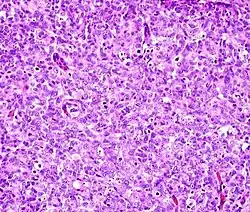

The most commonly used stain in histology is a combination of hematoxylin and eosin (often abbreviated H&E). Hematoxylin is used to stain nuclei blue, while eosin stains the cytoplasm and the extracellular connective tissue matrix of most cells pink. There are hundreds of various other techniques which have been used to selectively stain cells. Other compounds used to color tissue sections include safranin, Oil Red O, congo red, silver salts and artificial dyes. Histochemistry refers to the science of using chemical reactions between laboratory chemicals and components within tissue. A commonly performed histochemical technique is the Perls' Prussian blue reaction, used to demonstrate iron deposits in diseases like Hemochromatosis.[2]

The histological slides are examined under a microscope by a pathologist, a medically qualified specialist who has completed a recognised training program. This medical diagnosis is formulated as a pathology report describing the histological findings and the opinion of the pathologist. In the case of cancer, this represents the tissue diagnosis required for most treatment protocols. In the removal of cancer, the pathologist will indicate whether the surgical margin is cleared, or is involved (residual cancer is left behind). This is done using either the bread loafing or CCPDMA method of processing. Microscopic visual artifacts can potentially cause misdiagnosis of samples. Scanning of slides allows for various methods of digital pathology, including the application of artificial intelligence for interpretation.

Following are examples of general features of suspicious findings that can be appreciated from low to high magnification on histopathology: